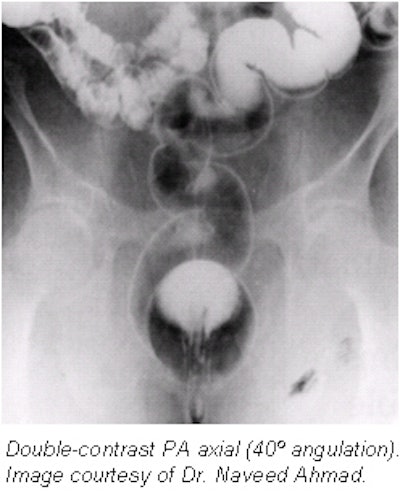

Patient positioning, imaging techniques for routine double-contrast barium enema

- After insertion of the rectal tube with the patient in the Sims position, tilt the table head down (-30º) and position the patient in the prone position. Release the control clip and fill the colon with barium (105% w/v). Out of 500 cc only 350 cc usually runs into the colon; the remainder of the barium will remain trapped in the tubing.

- Clamp the tubing and elevate the table to the horizontal position. Place the patient in the LPO position and begin slowly inflating the colon with air, using a pneumatic bulb while changing positions to left lateral, LAO, PA, RAO, and right lateral. Slowly administer four or five puffs in each position. When the barium is well in the right colon, stop inflating and position the patient prone.

- Elevate the table to about 80º while the patient is in the PA position. Unclamp the tubing and lower the enema bag to help drain the excess barium.

- Spot films.

- Rectosigmoid colon. After draining the excess barium, turn the table to the horizontal position. Inflate the colon with more air to distend the rectosigmoid colon, then take spot films of:

- Rectum. PA and left lateral.

- Sigmoid. LPO and right lateral.

- Flexures. Elevate the table to the upright (vertical) position and obtain spot film of the splenic flexure (RPO) and the hepatic flexure (LPO).

- Cecum. Decline the table to the horizontal position and obtain AP and LPO views of the cecum. If barium is retained in the cecum, use a lead glove to disperse the barium and turn the patient in LPO or RPO positions.

- Overhead films. All overhead films must be taken at 110 kVp; additional air should be insufflated before taking decubitus projections (approximately 5-7 pumps before each decubitus). No post-evacuation film is needed. All overhead films are obtained with the table horizontal. Suggested films that should be obtained are:

- PA to include rectum (14 x 17-inch, or 36 x 40-cm IR).

- 15º RAO with 35º tube angle caudad for sigmoid (14 x 17-inch, or 36 x 40-cm IR); three overhead films and five on a gurney against an upright bucky.

- Left lateral decubitus (14 x 17-inch, or 36 x 40-cm IR).

- Right lateral decubitus (14 x 17-inch, or 36 x 40-cm IR).

- Cross-table lateral rectum with patient prone and tip removed.

- Upright abdomen (14 x 17-inch, or 36 x 40-cm IR).

- The films must be evaluated by a radiologist before the patient leaves the department in case additional radiographs are needed to evaluate suspicious areas. If a lesion is suspected in the distal rectum, removal of the enema tip and additional radiographs will be necessary.